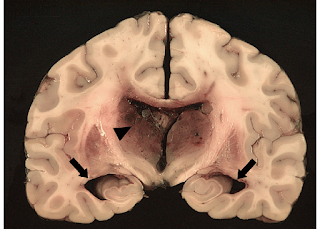

Hydrocephalus

is a condition in which an accumulation of cerebrospinal fluid (CSF) occurs

within the cavities of the brain.

This

accumulation of CSF causes increased pressure inside the skull. Hydrocephalus

can occur due to birth defects or can be acquired later in life.

Congenital

hydrocephalus is present in the infant prior to birth in the uterus during fetal

development. Most common cause of congenital hydrocephalus is AQUEDUCTAL

STENOSIS (narrowing of the aqueduct of Sylvius), which occurs when the narrow

passage between the 3rd and 4th ventricle in the brain is

blocked to allow sufficient CSF to drain. Therefore, fluid accumulates in upper

ventricles causing hydrocephalus.

Brain imaging

tests can show enlarged ventricles caused by the accumulation of excess of CSF. It

is also used to identify the underlying causes of hydrocephalus.